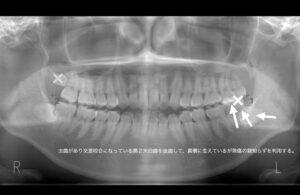

左上第2大臼歯が頬側に大きく逸脱し、本来噛み合う左下第2大臼歯とすれ違ってしまっている。

虫歯があり交差咬合になっている第2大臼歯を抜歯して、真横に生えているが無傷の親知らずを利用する。